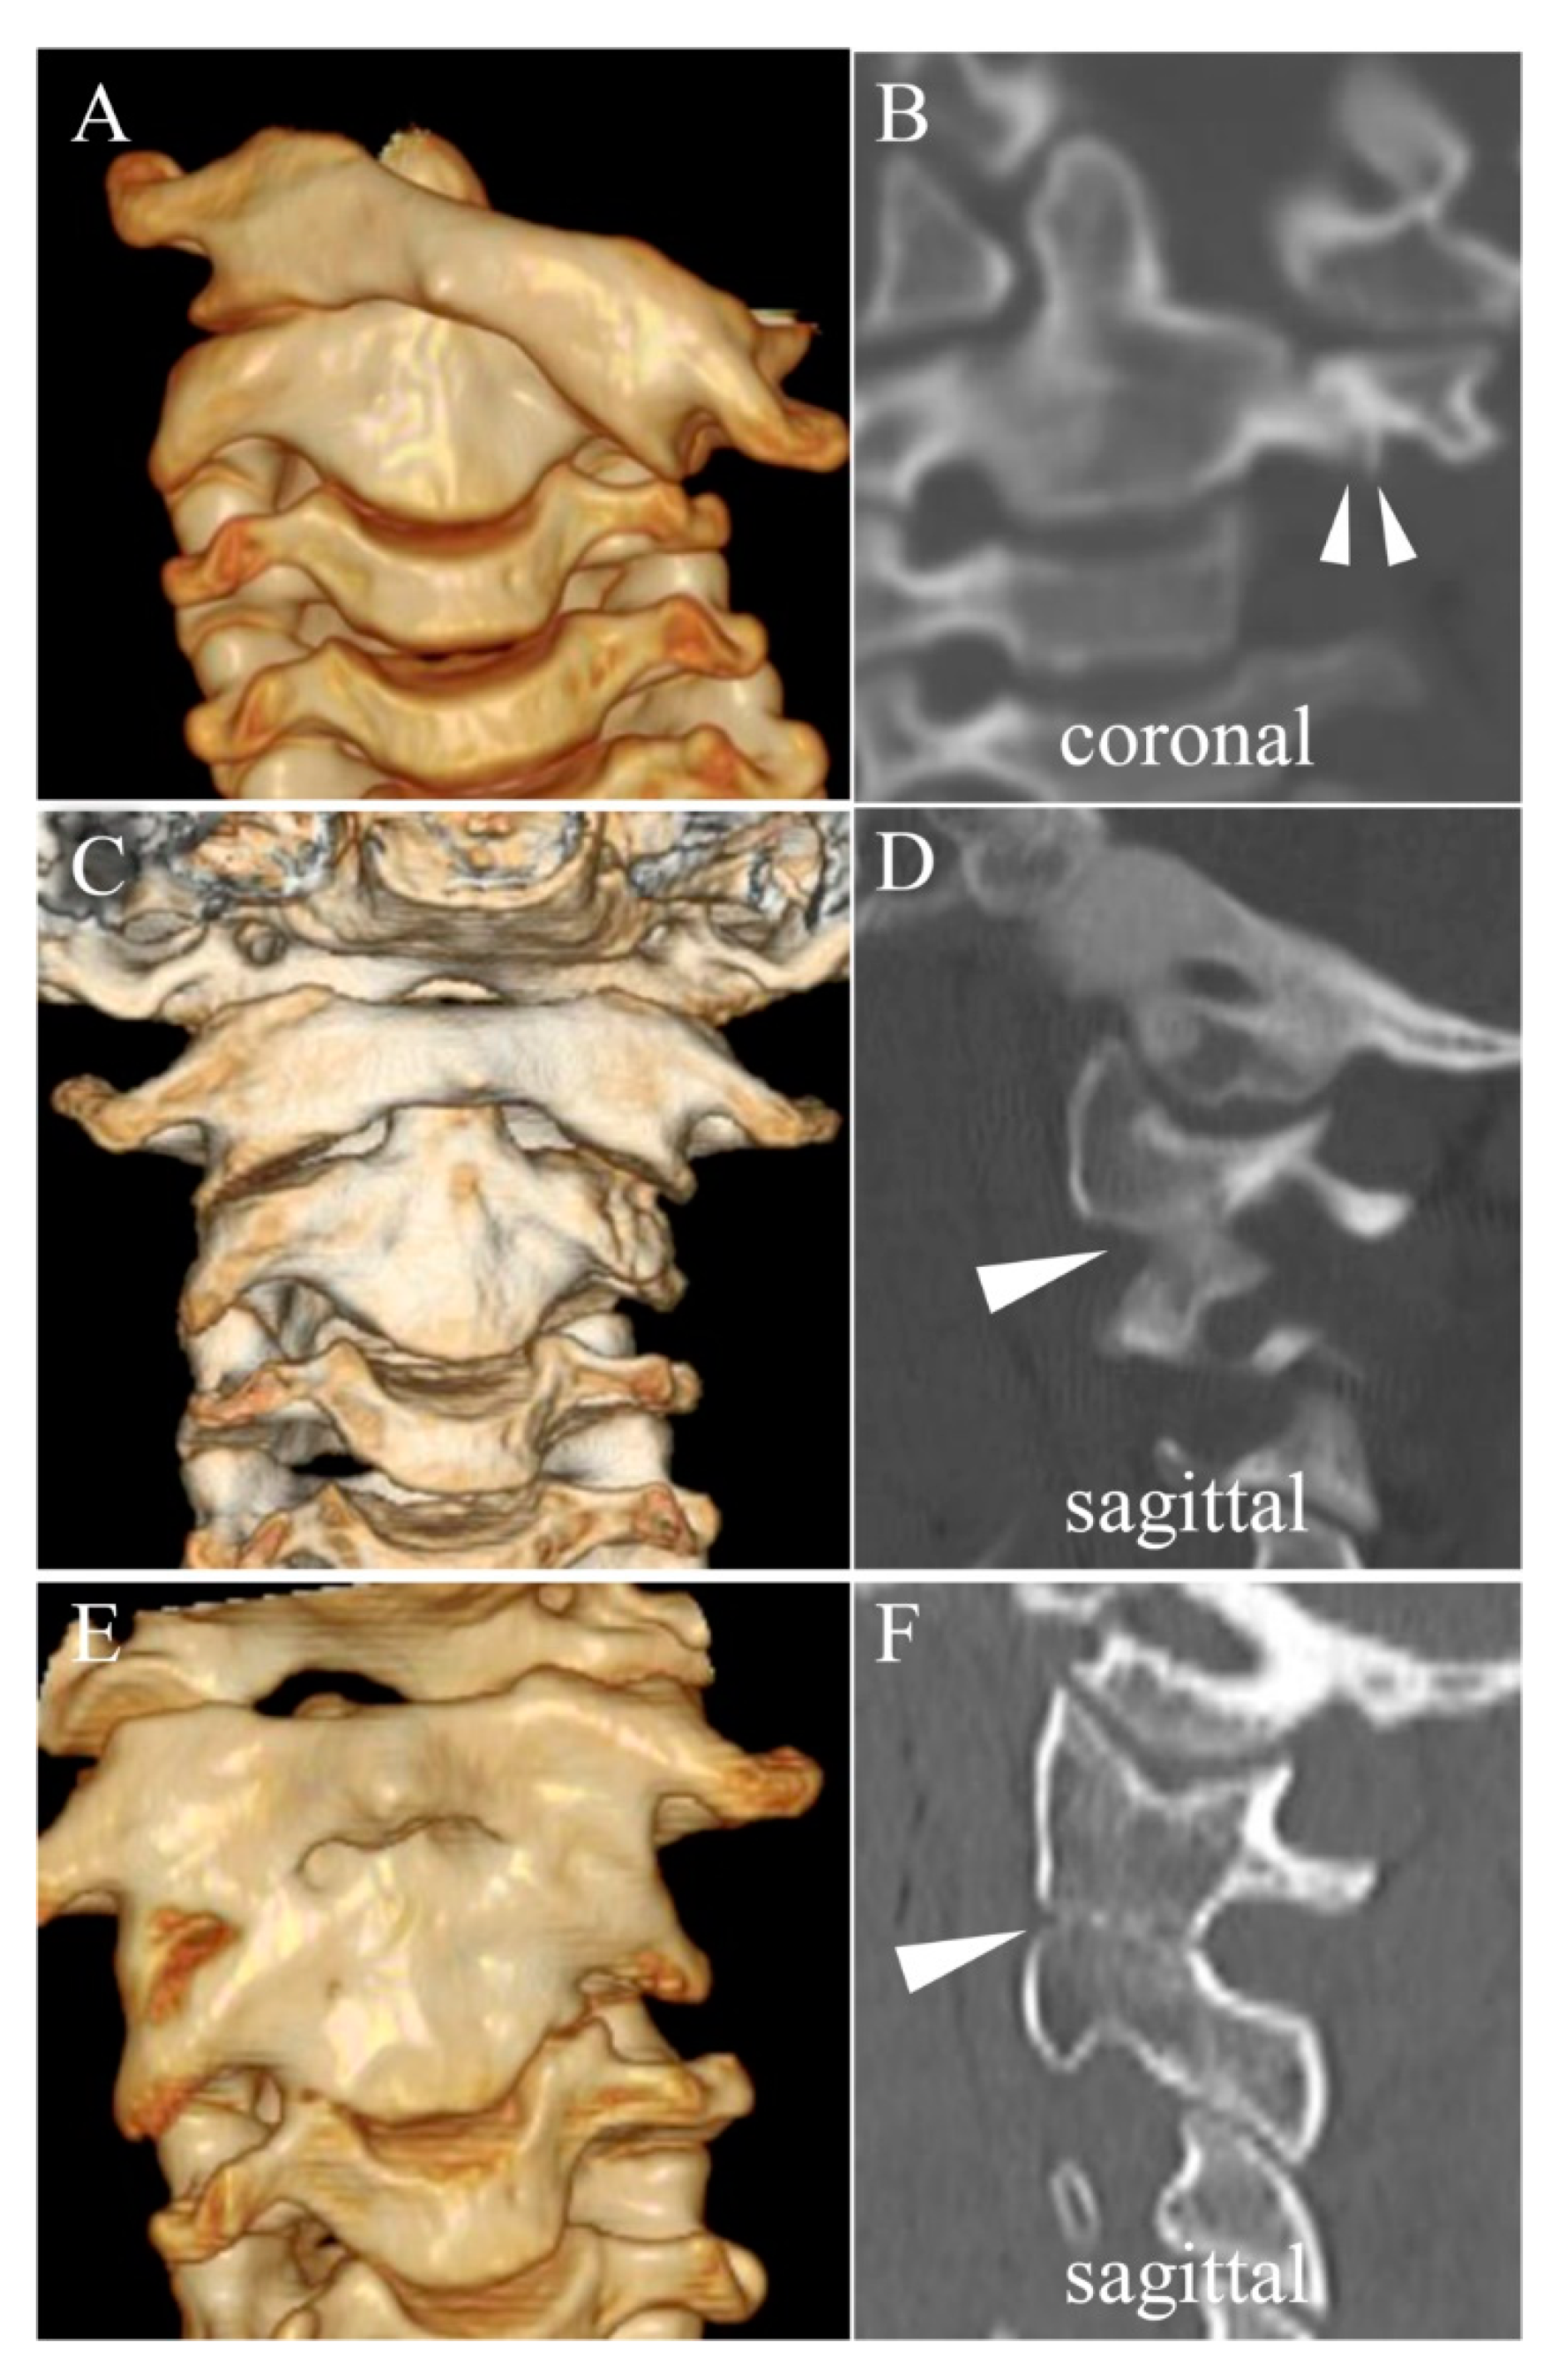

3.3. Direct Osseous Contact of the Facet Joint before and during Halo Fixation

4.1. Spontaneous Osseous Fusion after Halo Traction/Fixation

| SOF | Spontaneous Osseous Fusion of affected vertebrae which is confirmed after remodeling therapy for chronic AARF |

| DOC | Direct Osseous Contact of facet joints which is defined as disappearance of facet joint space between the adjacent vertebrae on sagittal or coronal CT images. |